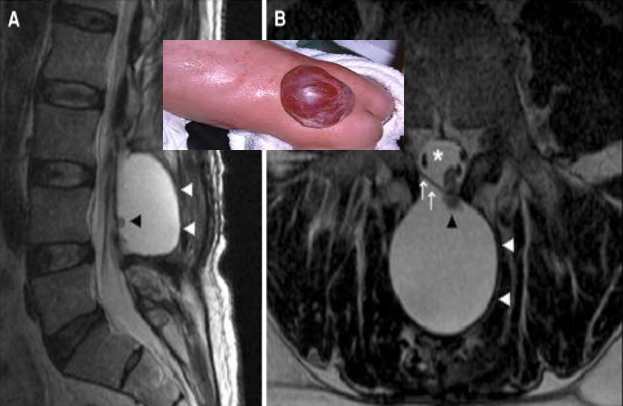

Meningocele:

Protrusion of meninges containing CSF